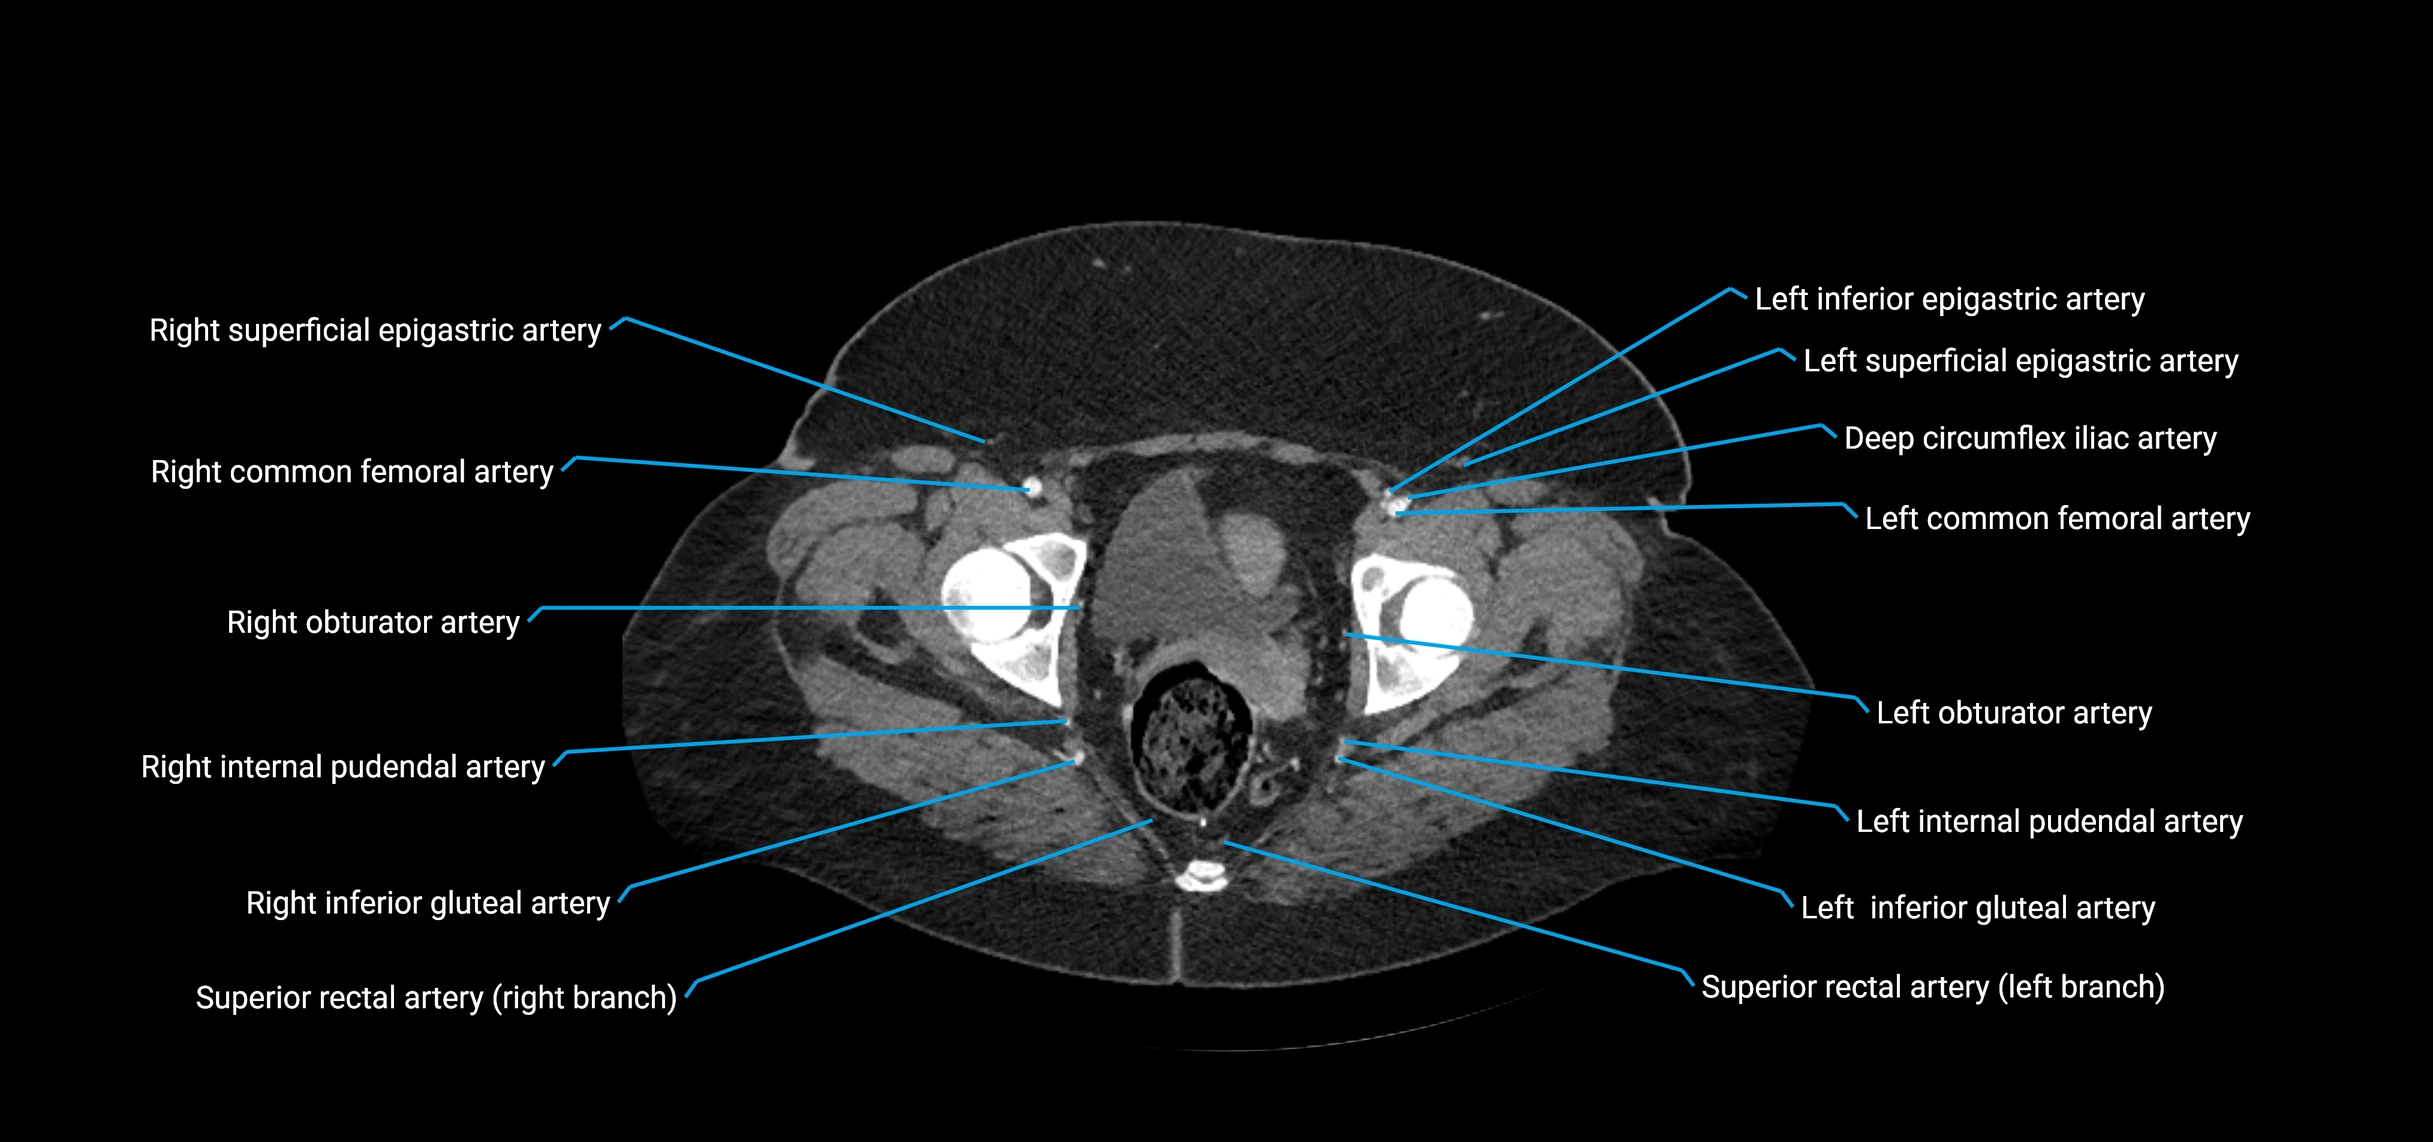

The abdominal aorta is the continuation of the thoracic aorta, beginning at the level of the aortic hiatus of the diaphragm (T12 vertebra) and terminating at the level of the L4 vertebra where it bifurcates into the right and left common iliac arteries. It lies slightly to the left of the midline and courses anterior to the vertebral bodies, surrounded by the retroperitoneal structures of the abdomen.

The abdominal aorta gives off numerous visceral and parietal branches, supplying the abdominal organs, pelvic structures, and lower limbs. It is the main conduit of oxygenated blood from the heart to the abdomen and lower body. The aorta is clinically significant as the common site of aneurysm, dissection, atherosclerosis, and traumatic injury.

Branches

• Unpaired visceral branches: celiac trunk, superior mesenteric artery (SMA), inferior mesenteric artery (IMA)

• Paired visceral branches: middle suprarenal arteries, renal arteries, gonadal arteries (testicular or ovarian)

• Parietal branches: inferior phrenic arteries, lumbar arteries, median sacral artery

• Terminal branches: right and left common iliac arteries

CT images

image